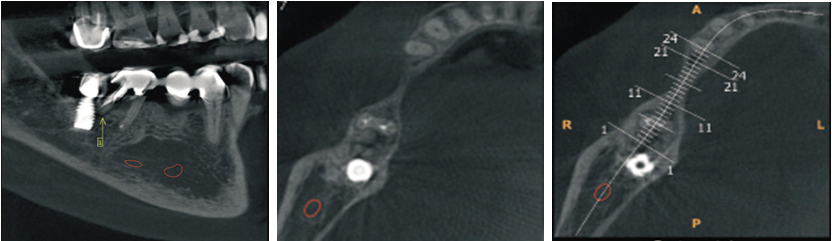

A 57-year-old female presented with a two-week history of left sided lower back pain associated with night sweats. No other constitutional symptoms were reported, and the patient’s physical examination was unremarkable. Past medical history of note included ischemic heart disease managed medically. The patient’s blood panel was within normal ranges, of note, serum electrolyte and hormonal studies (including CgA and plasma metanephrines) were normal, confirming the non-functional nature of the mass. Computed tomography (CT) revealed a large paraaortic mass, measuring 67 by 50 mm, extending from the adrenal gland to the mid lower pole of the left kidney (Figure 1A and Figure 1B). The mass enveloped the coeliac axis and superior mesenteric artery (SMA). No lymphadenopathy elsewhere was shown on positron emission tomography (PET) scan and fluorodeoxyglucose avidity was relatively low at 3.36, suggestive of no metabolic activity. Computed tomography guided biopsy of the mass was performed with the specimen sent for histopathological examination. This identified fragments composed of fibrous tissue and little adipose tissue with bland spindled cells (Figure 2A) and occasional ganglion cells (Figure 2B). No atypia or mitotic activity was evident. Flow cytometry was inconclusive for surface marker analysis. Histopathological examination was consistent with a diagnosis of ganglioneuroma. Due to the extensive vascular involvement of the coeliac axis and superior mesenteric artery, surgical excision was not considered to be appropriate and instead, due to the benign nature of the tumor and the mild symptomatology of back pain, regular surveillance was preferred. The plan for follow-up was for annual CT bought forward if symptomatology worsened, with re-evaluation of the surgical plan if required. Since diagnosis the patient has experienced an episode of back pain every six months, which resolves within a week. Further radiological imaging showed a stable lesion, with minimal growth, with a maximal transverse diameter of 81 mm and maximal height of 94.5 mm (Figure 1C). This case highlights a rare cause of back pain and retroperitoneal mass in an adult, and the diagnostic challenge that arises with this rare tumor.

Figure 1: Ganglioneuroma. (A) and (B) A large paraaortic mass, extending from the adrenal gland to the mid lower pole of the left kidney. (C) CT scan showcasing the lesion maximal transverse diameter of 81 mm and maximal height of 94.5 mm at further images.